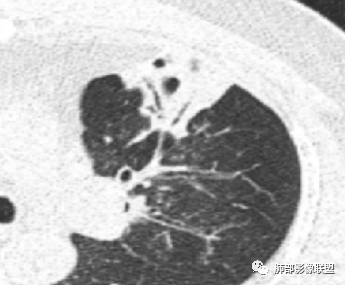

若晗: 结节十树芽十树雾

青藤之凉: 支原体肺炎的影像特征相对比较明显。有支气管壁增厚、支气管扩张样改变、支气管充气征。小叶小结节,有点状或者斑片状的浸润影、有实变影,表现为树芽征、树雾气征。

张延军: 树雾征,支原体感染

影像学特点:①支气管壁增厚、支气管周围炎。②腺泡结节、树芽征、树雾征(见病例1)。③结节融合,大片实变,部分边缘收缩。④分布上较广泛 。